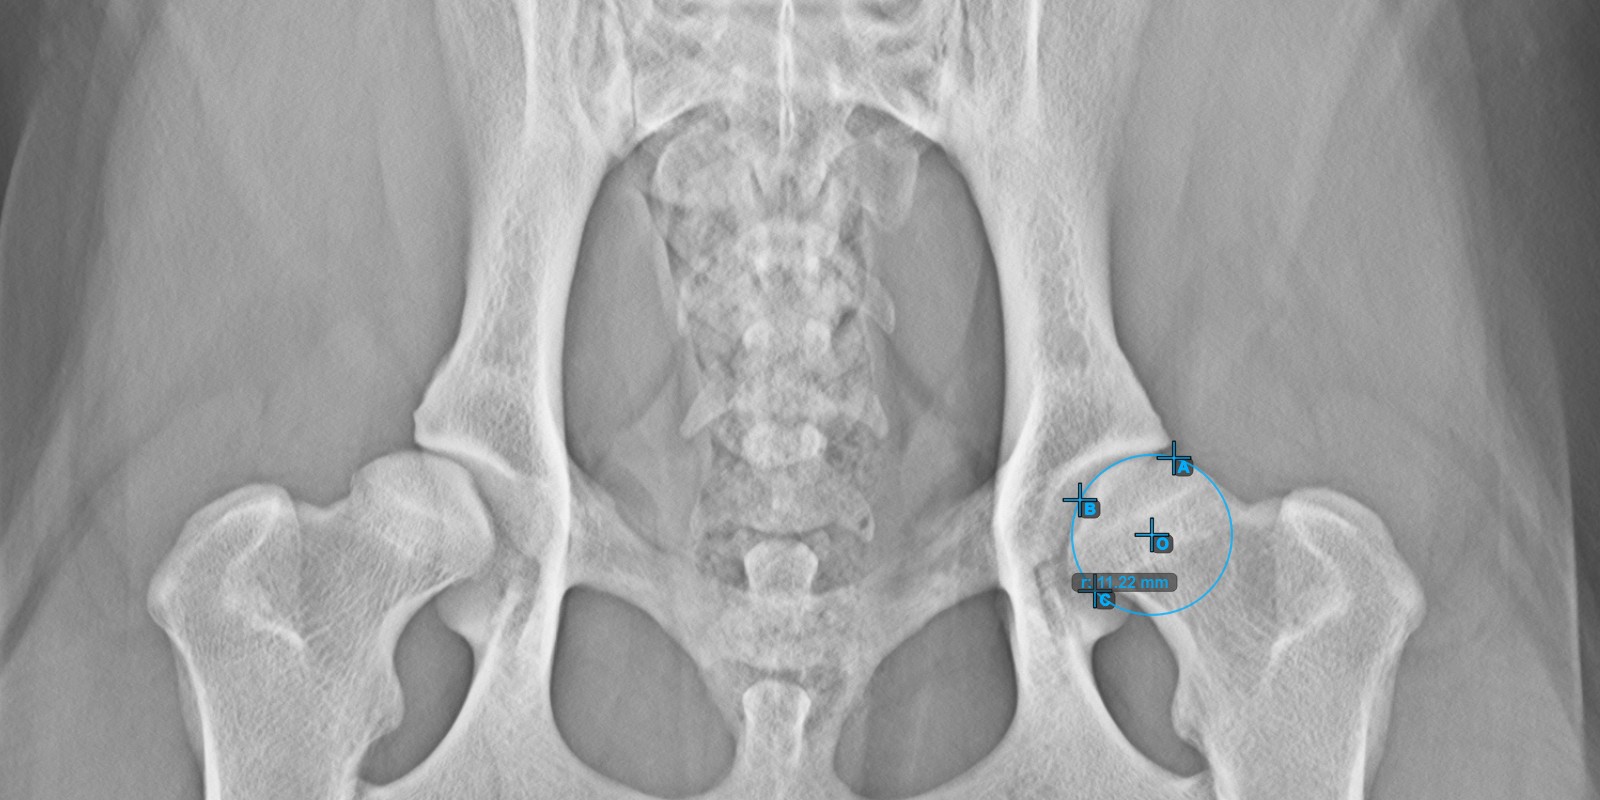

Calculate the left Norberg Angle measurement by marking a line on the effective edge of the left Acetabularis bone.

Mark a point near the left Caput Femoris and drag it along the effective edge of the left Acetabularis bone, forming the terminal side of the left Norberg Angle.

The drawn line must be a tangent to the effective edge of the left Acetabularis bone. The value and arc of the angle is automatically calculated.

The image below depicts the typical placement of the line and the calculated Norberg Angle measurement.